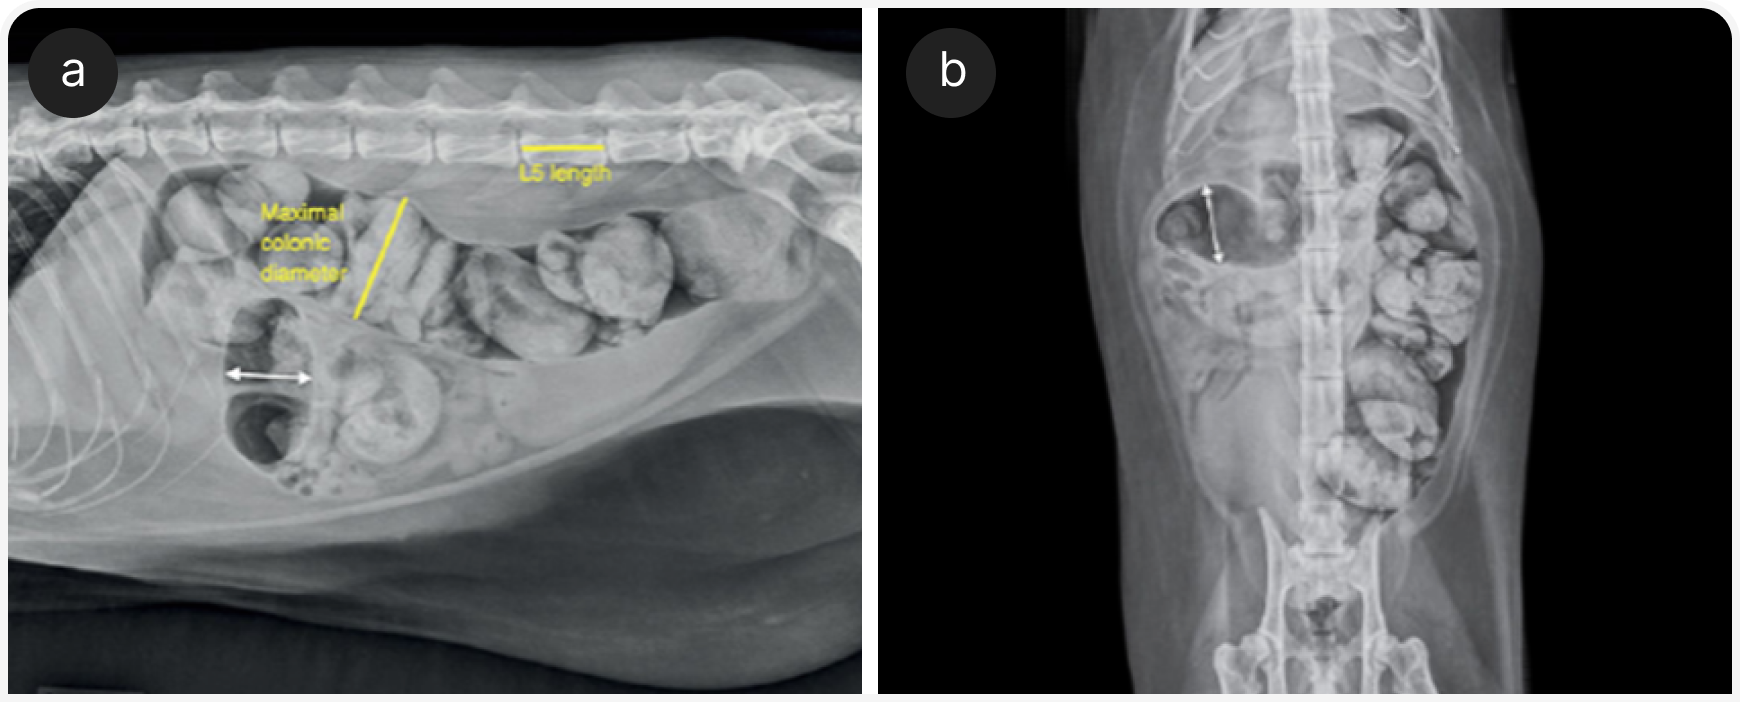

В исследовании 39 кошек с запорами или мегаколоном было рассчитано соотношение между максимальным диаметром толстой кишки и длиной пятого поясничного позвонка (L5) на боковых рентгенограммах. Значение больше 1,48 являлось хорошим индикатором мегаколона, в то время как у всех кошек с соотношением больше 1,62 был диагностирован мегаколон.